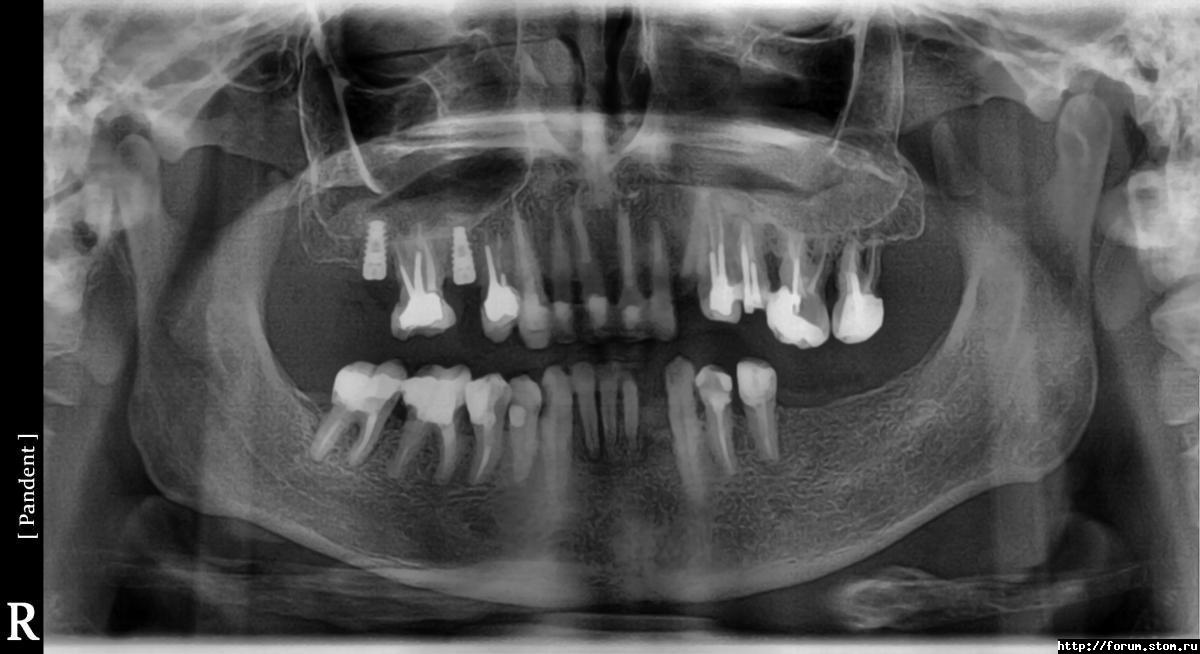

alexy78rus Опубликовано 7 ноября, 2011 Поделиться Опубликовано 7 ноября, 2011 Врач предлагает выдрать передние нижние резцы, обломанный верхний клык, и три верхних зуба слева(из за опущения).Замена всего этого хозяйства на импланты. Не слишком ли радикально? Предложите-покритикуйте план лечения Ссылка на комментарий